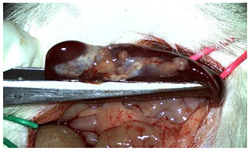

A well-established rat liver laceration model, known for its consistent induction of uncontrolled bleeding, was employed in this study [27]. Thirty-three male Wistar rats (weighing approximatively 350 g) were included. After intramuscular anesthesia (2:1 ketamine/xylazine), the surgical area was prepared. A xipho-subumbilical midline laparotomy allowed access to the left liver lobe, from where a 3 × 1.5 cm section was resected. Hemostasis was then achieved using one of three approaches: in the control group (C)—n = 5, bipolar electrocautery; in the study group (S)—n = 14, the novel CA–PLA hemostatic patch; and in the TachoSil® group (T)—n = 14, a fibrinogen/thrombin patch (TachoSil®—Corza Medical Gmbh., Jestetten, Germany), as presented in Table 1. Our study’s primary objective was to analyze the intracorporeal behavior of the new cyanoacrylate and polylactic acid hemostatic patch and compare it with Tachosil. For this reason, we allocated more subjects to these two key groups. We intentionally kept the control group smaller to adhere to the 3 Rs of ethical research: Reduce, Reuse, and Replace. For intraoperative footage concerning hemostasis, please refer to the Supplementary Materials (Videos S1–S3). Subsequently, the abdominal wall was closed with 4–0 polydioxanone sutures. Postoperatively, the rats were monitored for 24 h before being returned to their standard housing with ad libitum access to water and food.

The rats were observed for 150 days, with planned sacrifices at different time points (50, 100, and 150 days) to assess the liver resection site. After 50 days, five subjects from each of the S and T groups were sacrificed, followed by two more from each of these groups at 100 days. The remaining animals were sacrificed at the 150-day endpoint. For each sacrificed animal, the previously described anesthesia and laparotomy procedures were repeated. The clinical appearance of the abdominal cavity was documented, and after any adhesions were carefully dissected, tissue samples were harvested from the healed hepatic resection plane (approximately 3 × 0.5 cm strips) for histopathological analysis. Following the harvest procedure, the subjects were euthanized via an overdose of anesthetic.

The CA + PLA patch proved effective in achieving rapid hemostasis. Upon contact with the bleeding liver, it quickly polymerized and adhered, forming a hardened, shell-like barrier that immediately stopped blood flow. Observations at PO day 50 showed that the patch remained intact on the resection plane, alongside mild to moderate abdominal adhesions. By PO day 100, while the omentum largely covered the resection site, approximately 40% of the patch had degraded. By PO day 150, peritoneal adhesions were more significant (including stomach and small bowel involvement in two instances), yet the patch itself had undergone substantial degradation, with over 80% of its original size resorbed.

For the C group, the liver resection site showed minimal scarring and adhesions, consisting mainly of omental strips attached to the resected surface.

The subjects in the T group macroscopically displayed the fibrinogen/thrombin patch present at the resection plane at all time intervals. The patch appeared to thin over time, indicating its bioresorbable nature. Notably, this group developed the fewest peritoneal adhesions.

Table 2 illustrates the appearance of the hepatic resection plane for each study group at hemostasis and on postoperative days 50, 100, and 150.